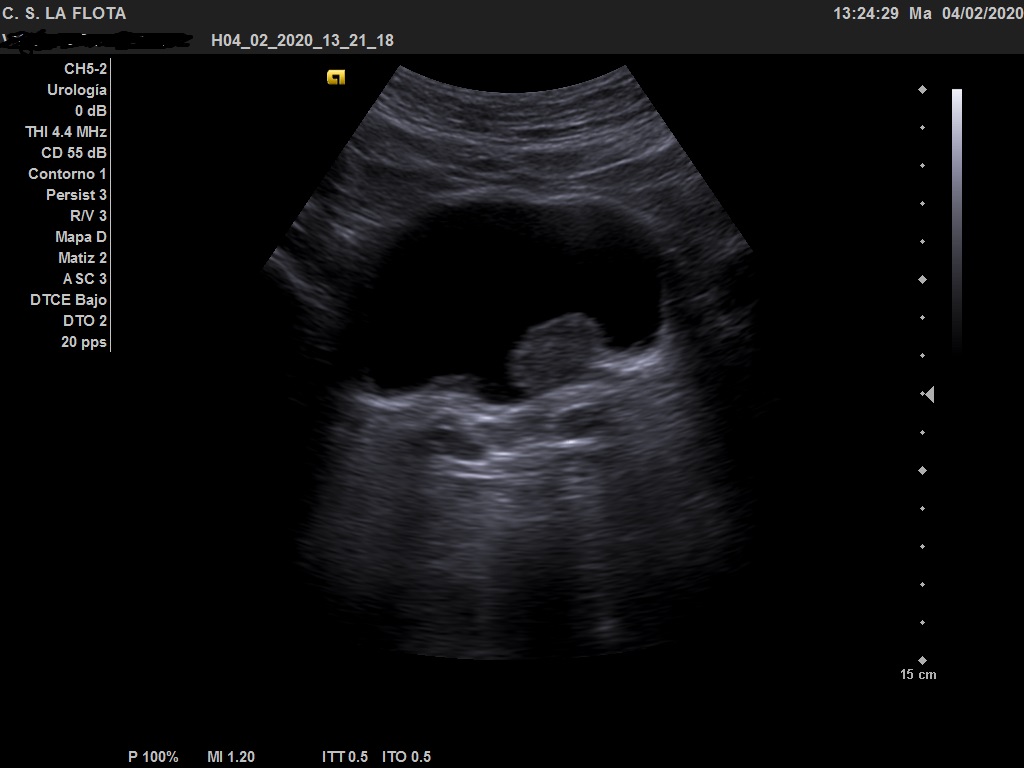

Ecografía clínica: riñones de tamaño y morfología normal, con buena diferenciación corticomedular y sin dilatacion de vias. En vejiga lesión polipoidea  de 25*18 mml.